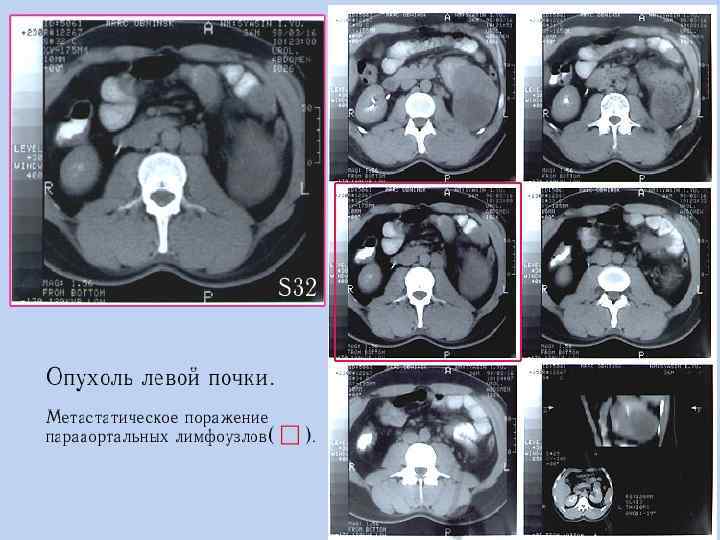

КТ – опухоль левой почки с массивным распространением.